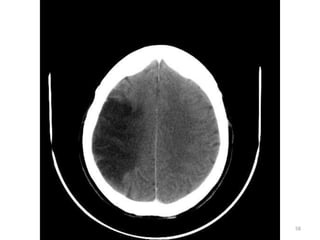

IMAGENS PATOLÓGICAS

AVCI/AVCH